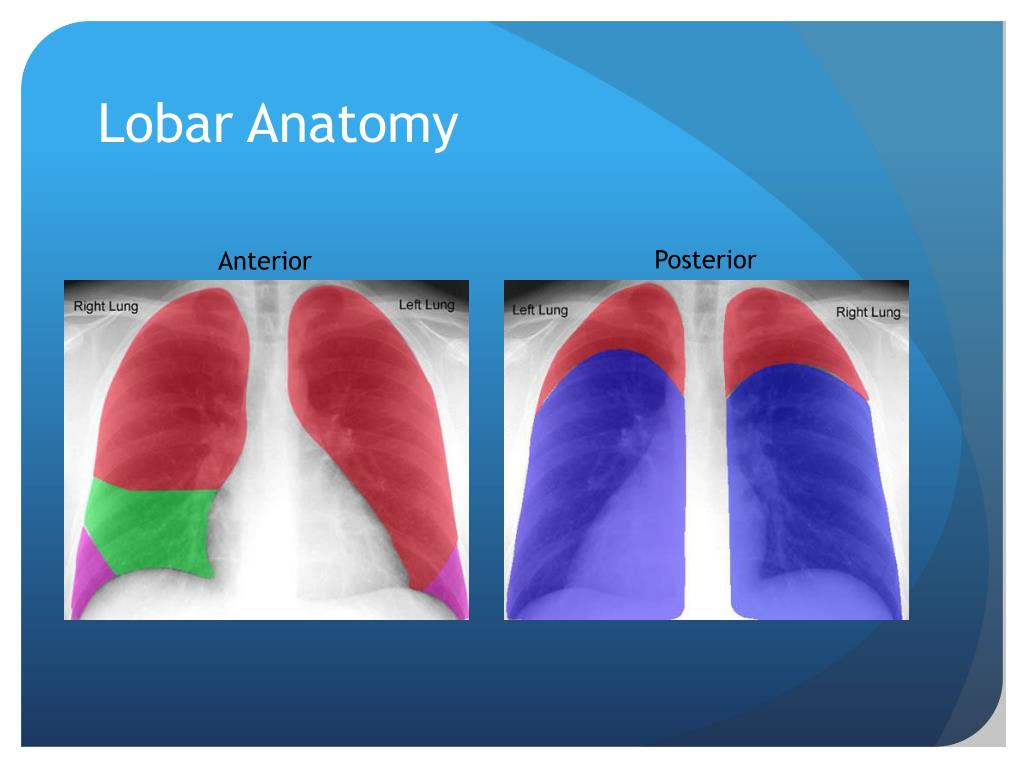

PPT - Chest X-Ray Interpretation for the Internist PowerPoint Presentation - ID:2033573  Holoprosencephaly causes, diagnosis, prognosis and treatment

PPT - Chest X-Ray Interpretation for the Internist PowerPoint Presentation - ID:934924  Lobar cxr anatomy

Lobar cxr anatomy  a Semilobar holoprosencephaly (according to occipitally inclined | Download Scientific Diagram